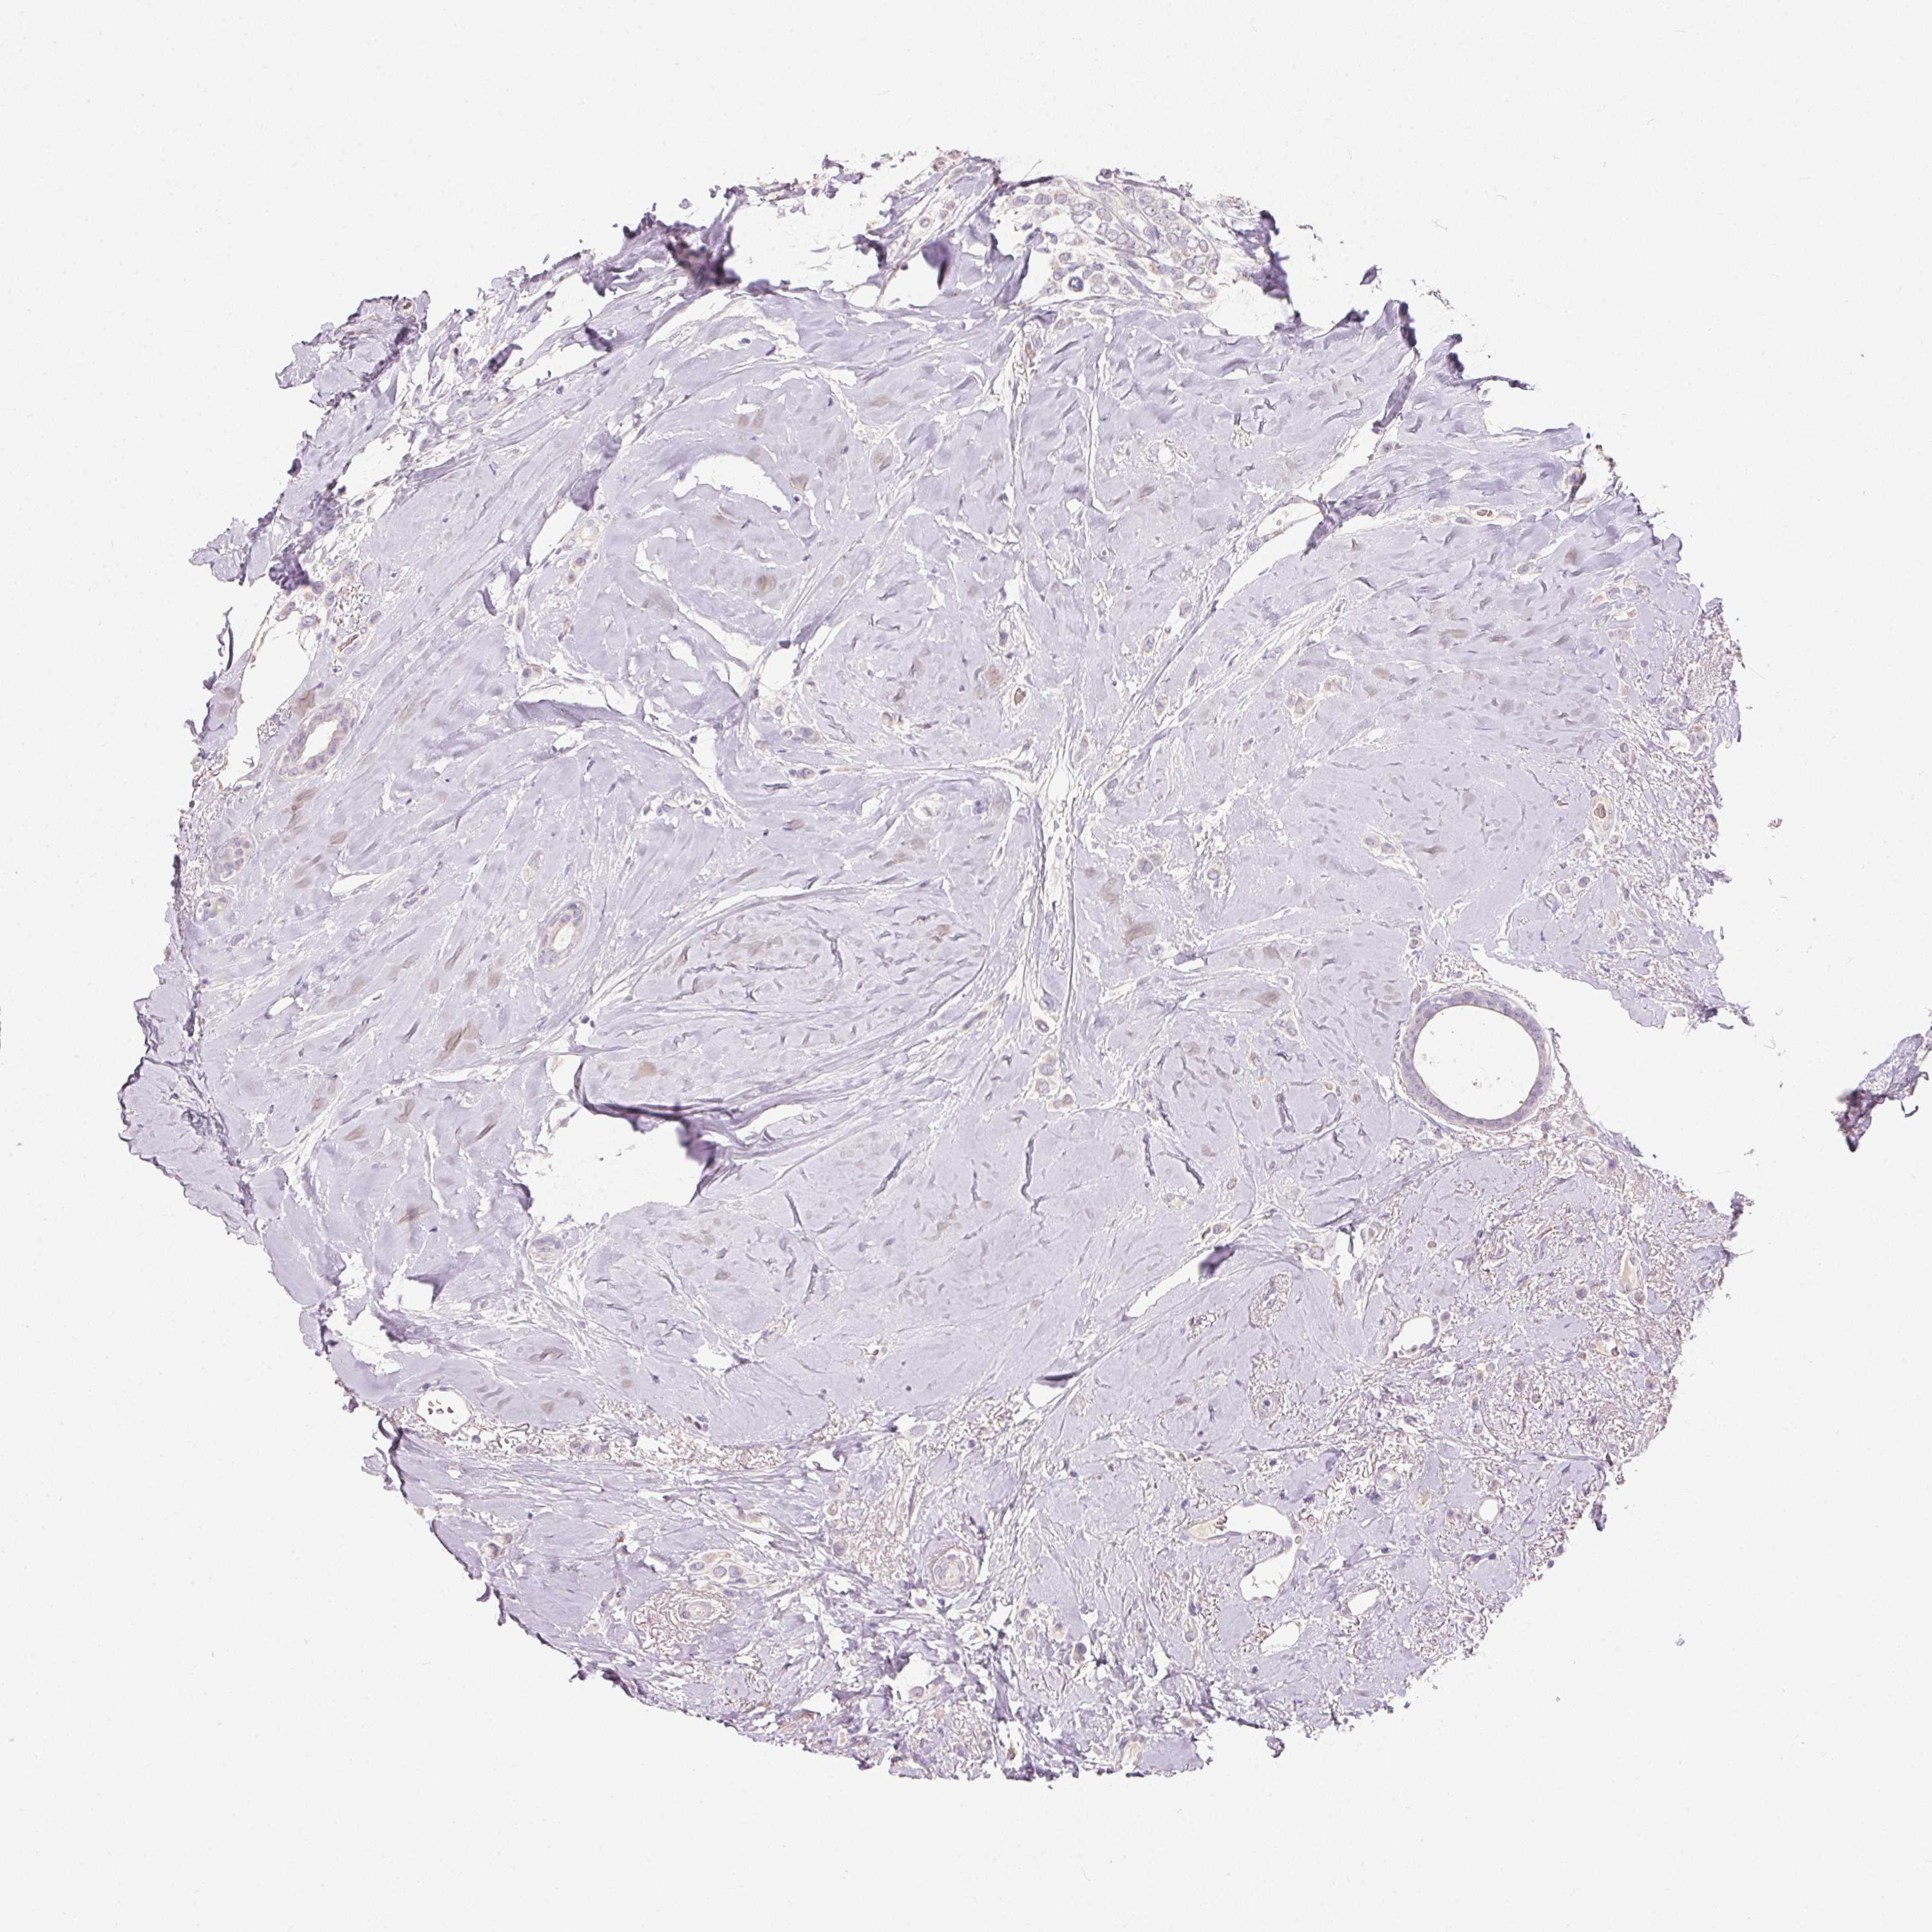

CANCER BREAST CANCER Show tissue menu

BRCA TCGA BRCA VALIDATION PROTEIN EXPRESSION

ANTIBODIES

AND

VALIDATION